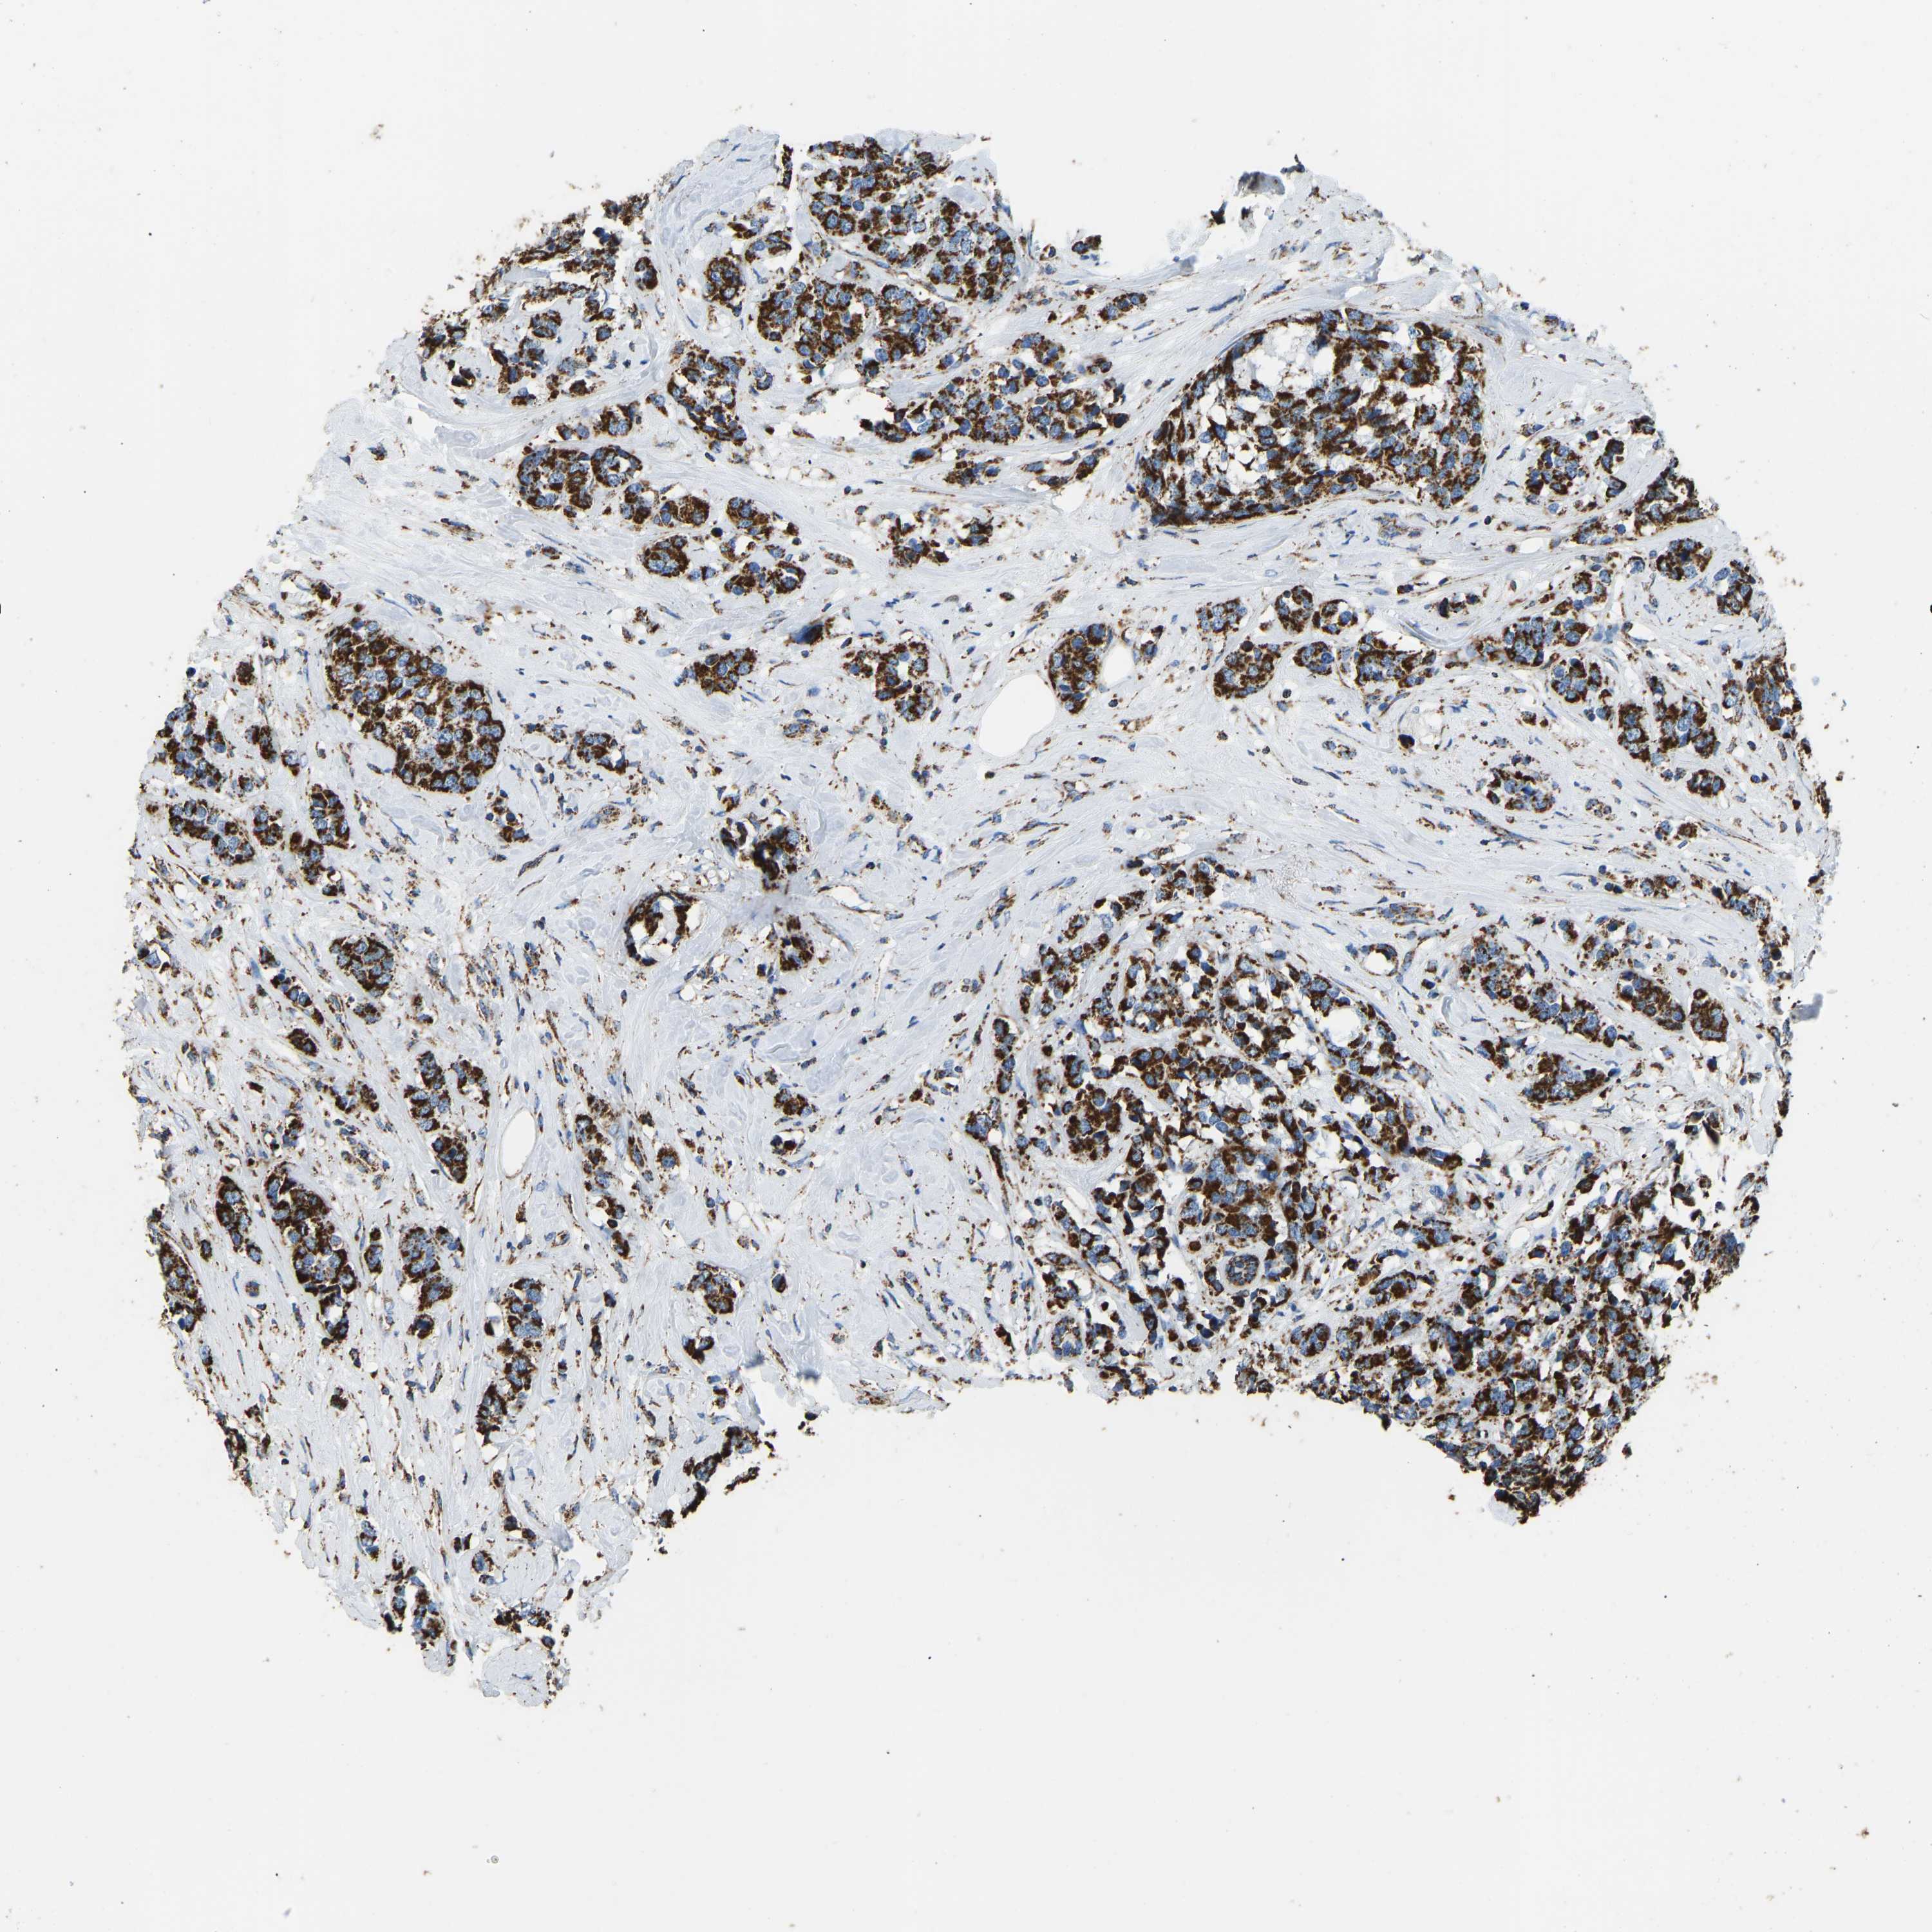

BRCA TCGA BRCA VALIDATION PROTEIN EXPRESSION

ANTIBODIES

AND

VALIDATION